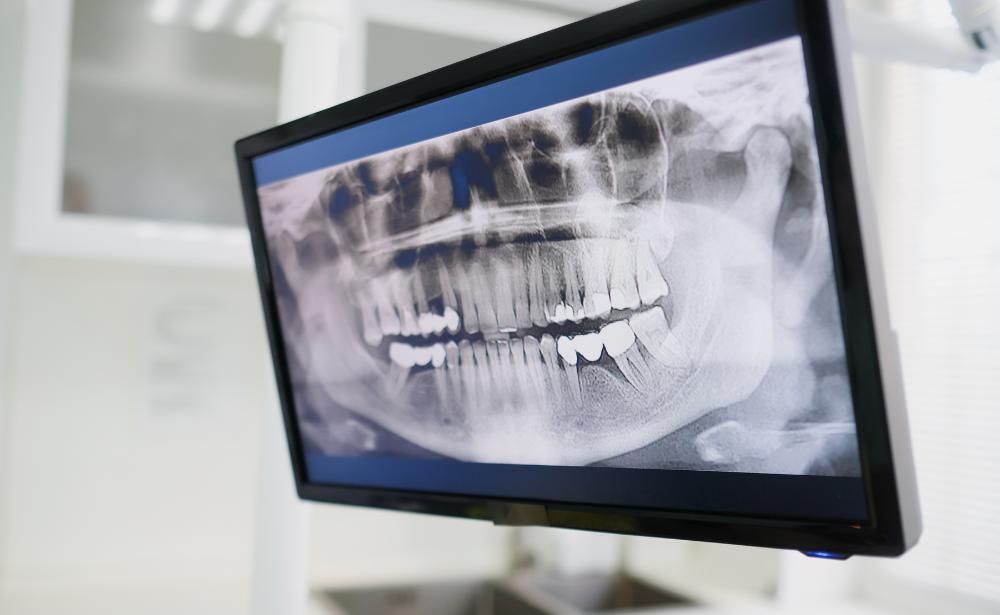

Smile O Care is not any ordinary dental clinic, but it is actually a Special Dental X-Ray Centre in Lucknow, India designed to cater to a large range of complicated medical diagnostic needs. Contemporary dentistry requires more than just the surface perception, but a three-dimensional perception of the individual oral structure of each patient. We have high-tech sensors and state of the art imaging software in our centre, which provide real-time results on our chair-side monitors. This enables Dr Soni Giri to communicate with you in real-time about the state of your oral health and display to you precisely what the problems are and not merely tell you about them.

A localised perspective is not usually adequate when a thorough treatment plan is involved, in particular, orthodontic braces, dental implants, or wisdom teeth extractions. Smile O Care boasts of having the Best OPG Dental X-ray in Lucknow. An orthopantomogram (OPG) is an image that gives you a panoramic view of all your oral structures in one image, which is detailed. This is essential in determining the relative location of the affected wisdom teeth and their relative location with the mandibular nerve, which will result in extractions being made as safe and as precise as possible.

We have ensured that our equipment, the Best OPG Dental X-Ray in Lucknow, is patient-centric in design. The OPG is extraoral, as opposed to the intraoral X-rays, which require the insertion of sensors into the mouth. The machine will spin around your head without you moving, and therefore is a great choice for patients having a sensitive gag reflex. This wide shot view enables Dr Soni Giri to identify cysts, tumors and irregularities of your jaw that may otherwise be overlooked on small-sized film and gives you a bigger picture of your facial skeleton and the arches of your teeth.